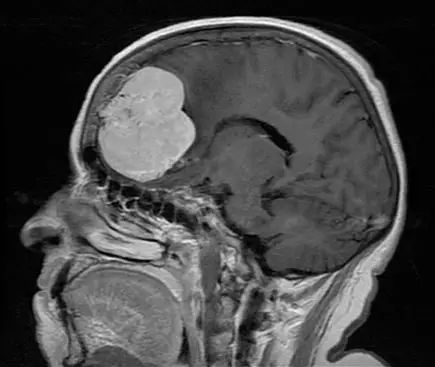

下图所示的转移瘤为脑膜瘤的另一种常见鉴别诊断。这些轴位(左)和冠状位(右)T1WI增强扫描显示肿瘤基底位于硬脑膜,并可见强化。与脑膜瘤相比,其强化较为不均匀,且边缘不规整,提示存在脑浸润。手术时,软脑膜和皮质下发现有肿瘤浸润,后竟证实为转移性直肠癌。